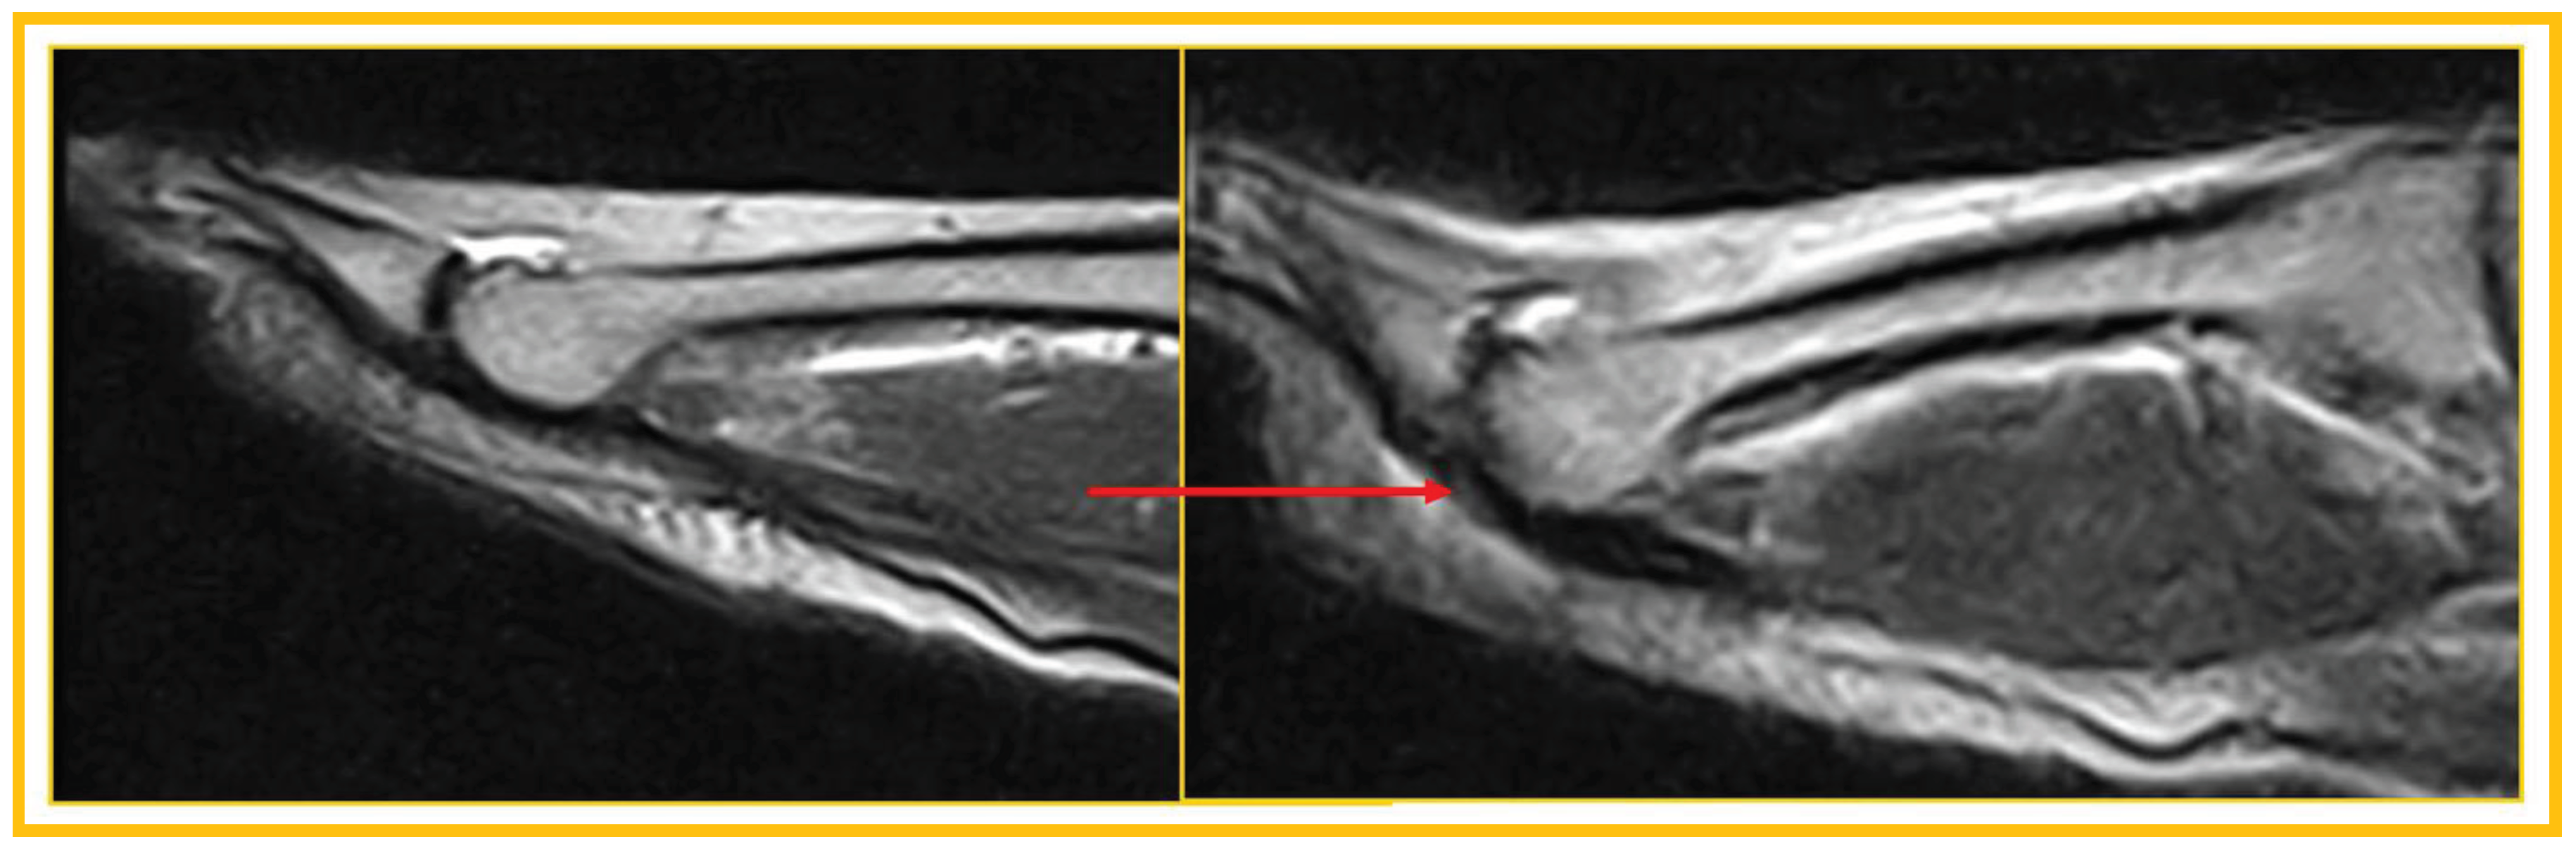

Patient 7: symptomatic (54 years, man). False negative (laxity): Symptomatic patient, negative for PP lesion both in standard position and during ST. Laxity in the absence of a lesion was later confirmed at revision surgery (Figure 8).

Figure 8. False negative (laxity).